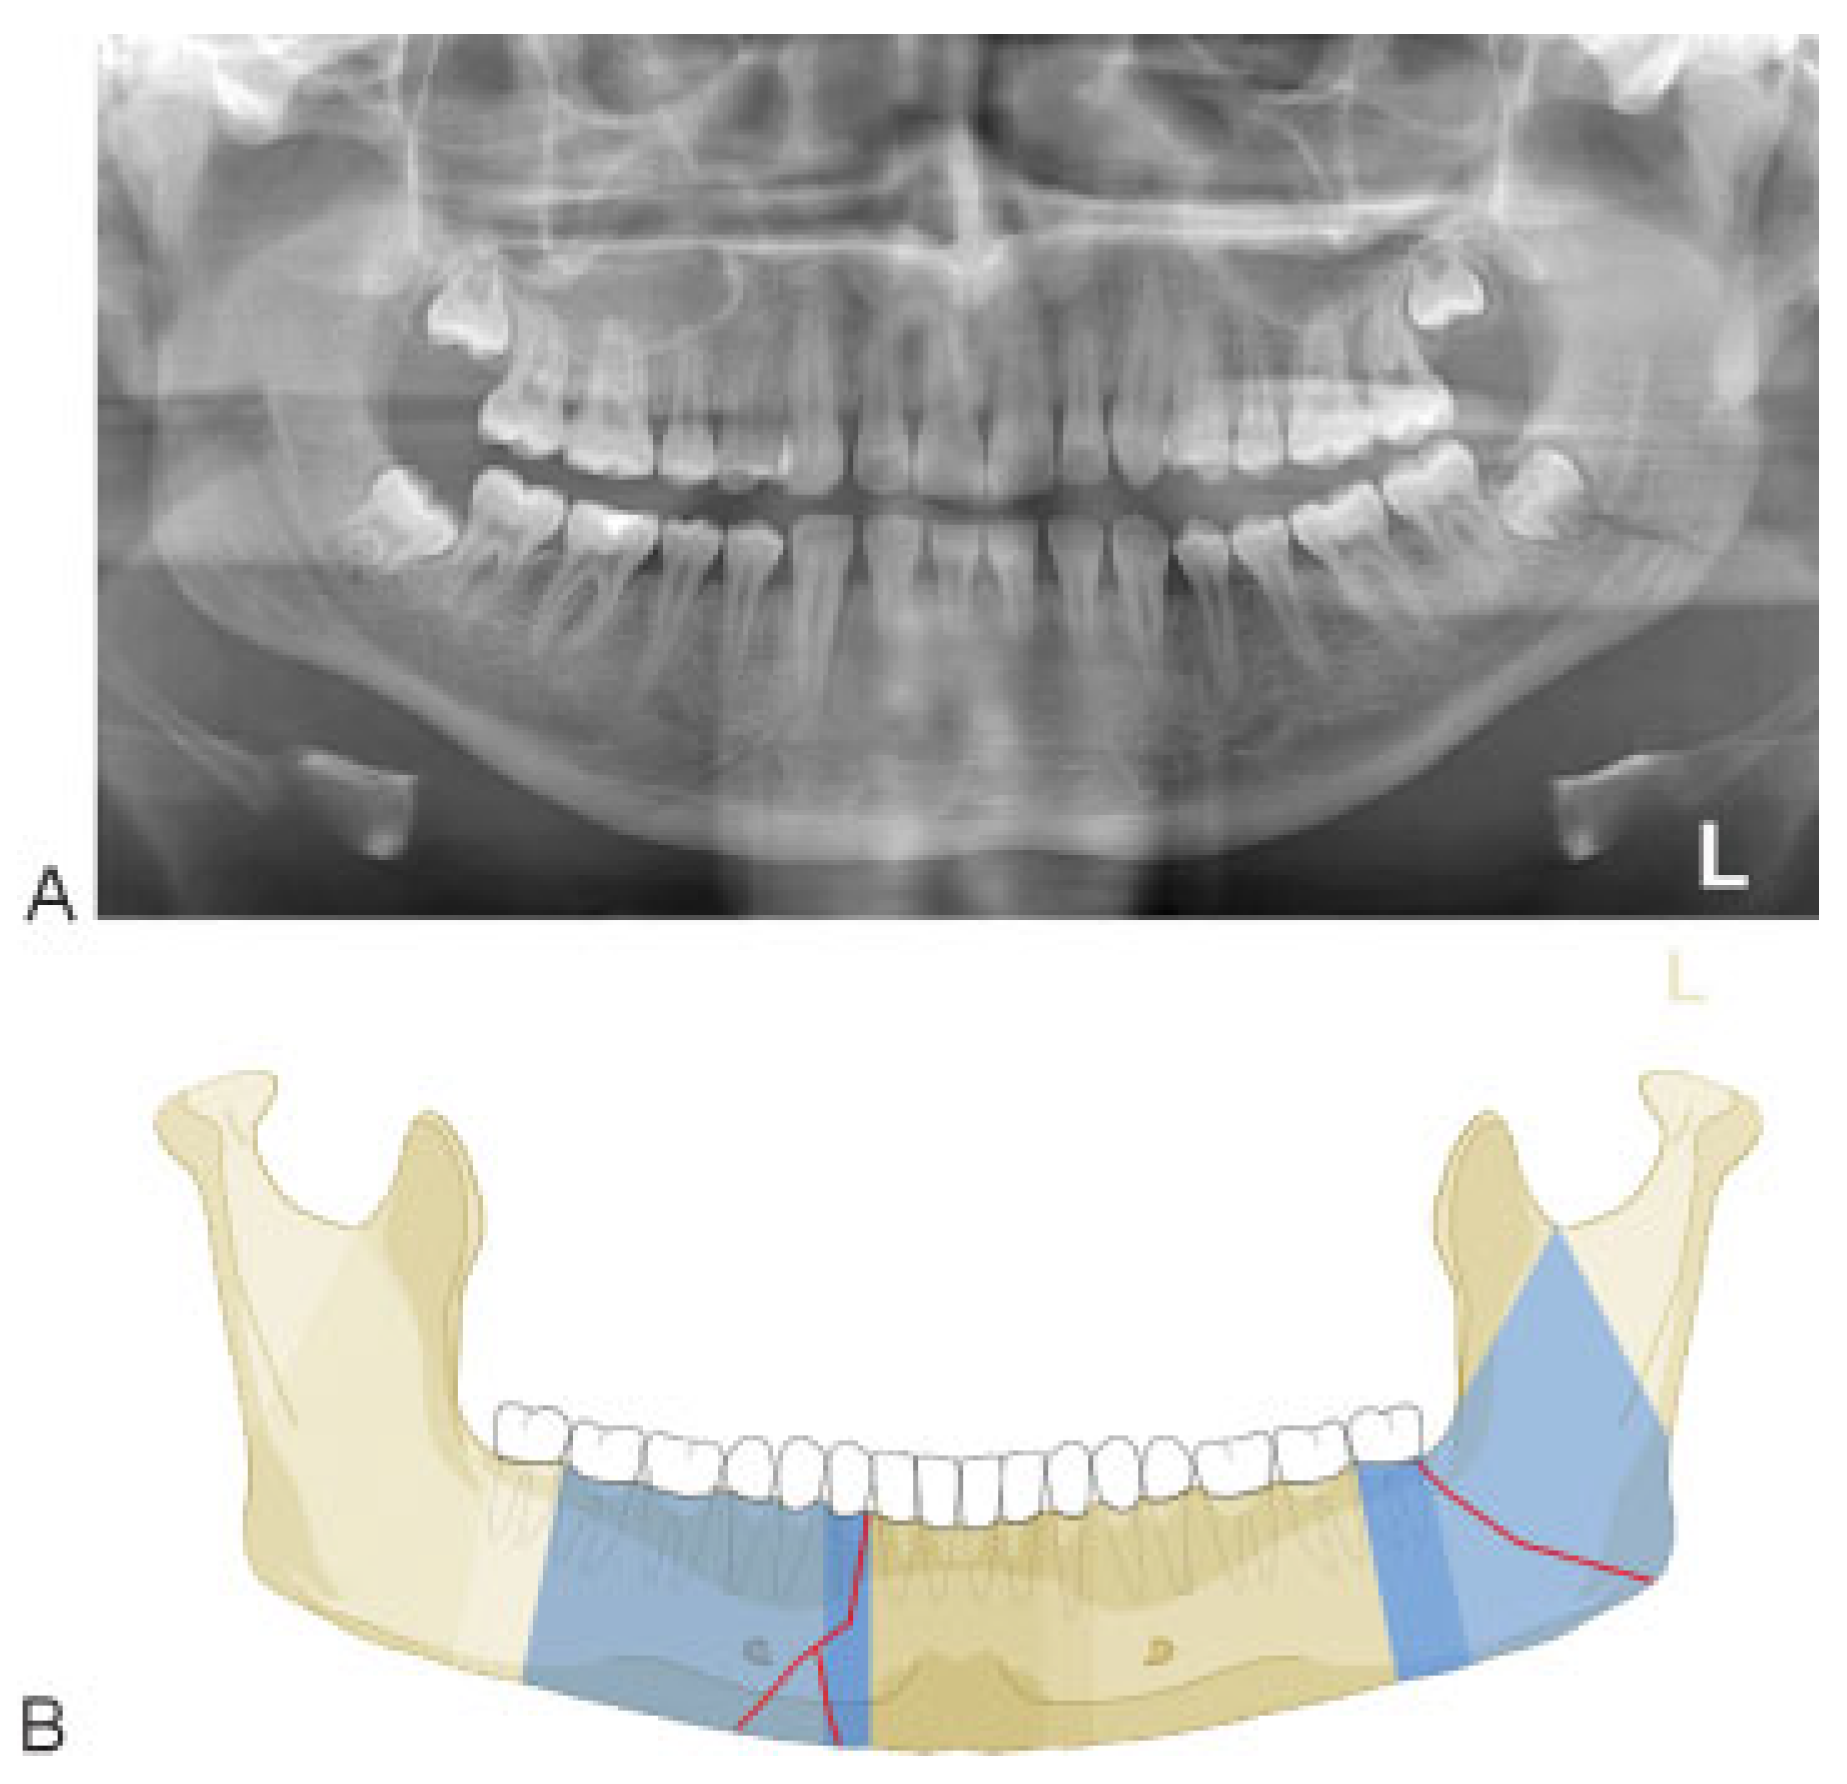

:Anatomical and Diagnostic Imaging Considerations

Mandibular Body Region

Case Examples